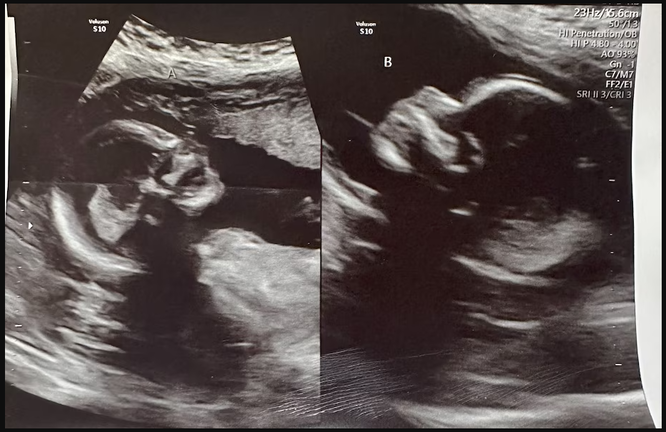

Dünya çapında kadınların sadece yüzde 0,3’ünde iki rahim vardır ve her bir rahimde hamilelik daha da nadirdir. Nadir görülen çift rahimle doğan Alabamalı bir kadın, her rahimde bir tane olmak üzere iki bebeğe hamile.

32 yaşındaki Kelsey Hatcher 17 yaşındayken çift rahimli olduğunu öğrendi. Bu son derece nadir görülen anomali kadınların yaklaşık yüzde 0,3’ünde görülür. Her iki rahimde de bebek taşımak ise daha da nadir görülen bir durumdur.

Uzmanlar, “her fallop tüpüne, yani rahmin her iki tarafına bir yumurta girmiş ve ardından sperm her bir rahme girmiş ve döllenme ayrı ayrı gerçekleşmiş” olmasının muhtemel olduğunu söylüyor.

Böyle bir olayın gerçekleşme olasılığının 50 milyonda 1 olduğu düşünülmektedir. Bangladeş’te böyle bir şey en son 2019 yılında yaşanmış, bir kadın ilk çocuğunun erken doğumundan 26 gün sonra ikinci ikizini dünyaya getirmişti.